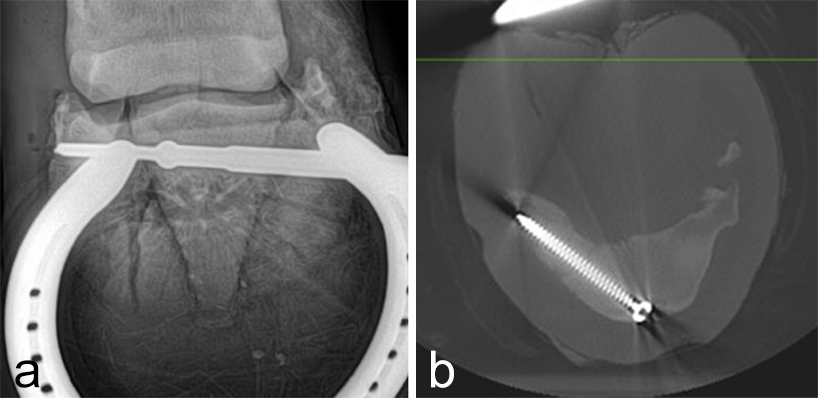

The horse was routinely anesthetized and positioned in left lateral recumbency to be able to access the medial aspect of the left forelimb. The lower limb was aseptically prepared and draped appropriately to isolate the solar region of the hoof from the surgical area, and to allow visualization of the coronary band. The targeting clamp was assembled with the straight outer sleeve and the 4.5 mm drill sleeve. It was positioned under radiographic and image intensifier guidance in an oblique direction to avoid drilling through the proximal hoof wall. Once the surgeons were satisfied with the position of the targeting clamp, the location of the trocar was marked on the draping and a stab incision was made at the level of the outer sleeve. The outer sleeve was inserted in the skin incision and the adjustable rail of the targeting clamp was tightened. The 4.5/3.2 mm insert sleeve followed by the 3.2/1.6 mm insert sleeve (provided in the 4.5 mm headless compression screw kit) were placed in the 4.5 mm drill sleeve (Fig 7).

A 1.6 mm guide wire was advanced through the bone to assess the correct positioning of the targeting clamp. The guide wire is centered within the cyst. At this stage, the ideal screw length was measured on the perioperative radiographs. When using these headless cannulated compression screws, remember that the shaft thread length is approximately 40% of the screw length. Ideally, the threaded shaft of the screw is positioned on the trans-side of the cyst. The 3.2/1.6 mm insert sleeve was then removed and the bone was drilled with a cannulated 3.2 mm drill bit to the required length (Fig 8a). Considering the high-bone density at this location, the entire length of the drill hole was tapped by hand with a cannulated 4.5 mm tap through the 4.5 mm drill sleeve. Next, a 4.5 mm headless compression screw was inserted through the 4.5 mm drill sleeve and tightened by hand (Fig 8b). The stab incision was closed routinely. The horse was covered with a two-layer bandage. The total surgery time was 30 minutes.